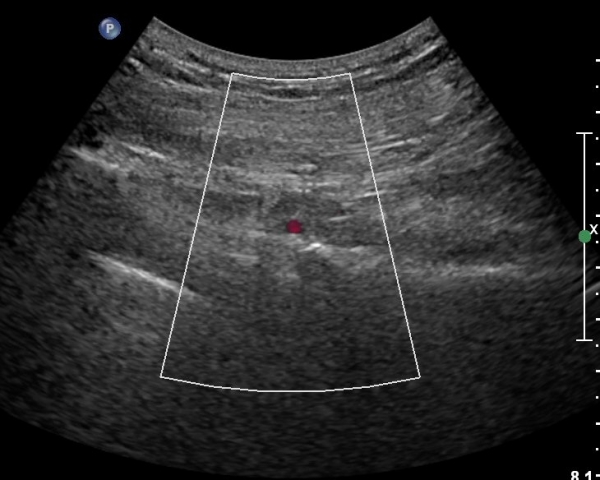

ÈÄ»óÀå°ñ±Ø ¿ÜÃø¿¡ ŽÃÊÀÚ¸¦ ¼öÆòÀ¸·Î ´ë¸é ½ÉÃþÀ¸·Î Àå°ñÀÌ °üÂûµÇ°í Àå°ñ Ç¥Ãþ¿¡ ´ëµÐ±Ù°ú ÁߵбÙÀÌ °üÂûµÈ´Ù(»çÁø 1).